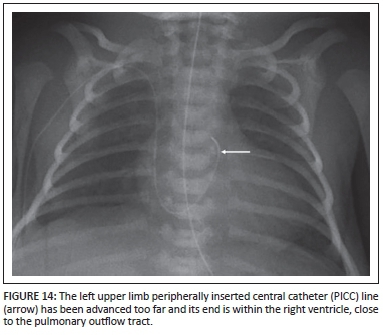

The peripherally inserted central catheter (PICC) is inserted into peripheral limb veins, with the end lying in the distal SVC or at the cavo-atrial junction. Common complications are related to insertion and malpositioning (Figure 14). Correctly positioning it is important for the administration of certain intravenous medications.